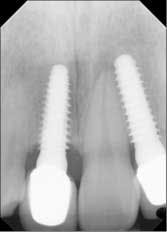

Fig. 8a: One year post-insertion — final radiographs.